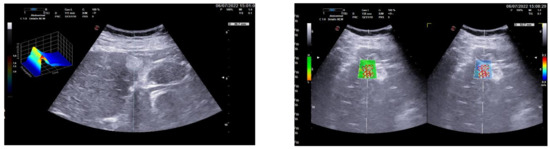

3.1. Group 1: Benign Focal Liver Lesions (Hemangiomas)

3.2. Group 2: Malignant Focal Liver Lesions (Hepatocellular Carcinoma)